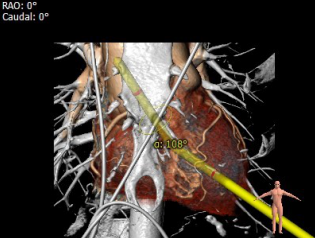

瓣环:27mm;LVOT:26.8mm;STJ:37.9mm;升主动脉:37.4mm;左冠高度:20.2mm;右冠高度:28.9mm;钙化积分:18mm3;瓣环与水平面夹角:29°;心尖入路夹角:108°。

1. 首选经心尖入路,植入29mm J-Valve瓣膜。经心尖入路夹角偏小,输送系统需预弯。